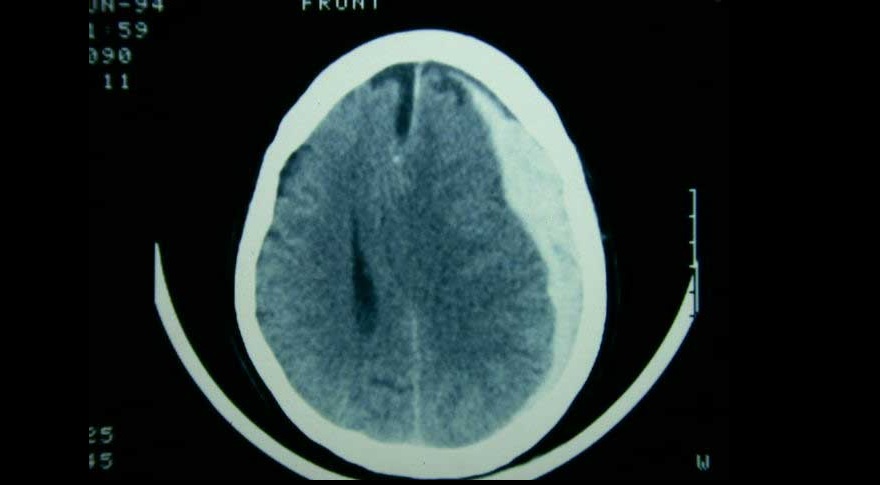

Tres ensayos clínicos exploran la utilidad de la embolización de esta arteria en el manejo del hematoma subdural subagudo o crónico, con miras a reducir la tasa de recurrencias y la necesidad de nuevas intervenciones. New England Journal of Medicine, 20 de noviembre de 2024.

El tratamiento de pacientes con hematoma subdural agudo difiere según el centro de tratamiento, debido a la variación en el abordaje preferido. Una estrategia de tratamiento que prefirió un enfoque agresivo de evacuación quirúrgica aguda sobre el tratamiento conservador inicial no se asoció con un mejor resultado funcional. The Lancet Neurology, 5 de mayo de 2022.

Un ensayo clínico mostró que el corticoide se asoció a peores resultados clínicos a los seis meses en comparación con placebo, pero con menor cantidad reoperaciones. New England Journal of Medicine, 16 de diciembre de 2020.